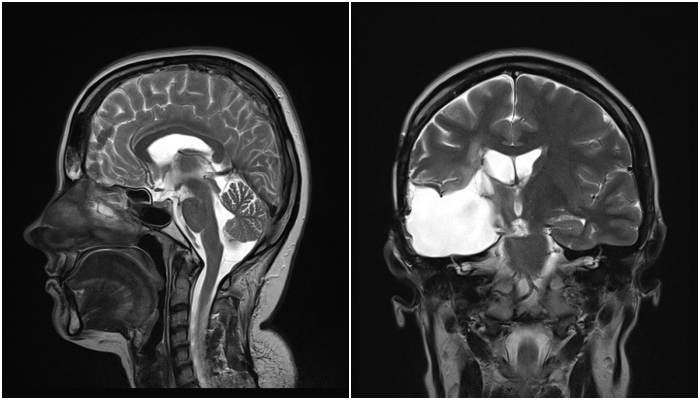

Lekarze wykonali mi tomografię komputerową. Na moim mózgu wyrósł olbrzymi guz. To on, a nie zmęczenie, był przyczyną wszystkich bólów głowy. Kiedy usłyszałam, że mam raka, tę najstraszniejszą z chorób, której sama nazwa wzbudza lęk, próbowałam to wszystko wyprzeć. Myślałam, że to tylko zły sen, że zaraz się obudzę. Przecież takie rzeczy się nie zdarzają, nie tak młodym ludziom, nie mnie… Pamiętam nerwowe szepty lekarzy, szloch mamy i zapadające jedna po drugiej decyzję. Czułam, że gdzieś na szali waży się moje życie, a ja na nic nie mam wpływu. Zdecydowano, że trzeba natychmiast mnie operować, a rodzicom nie pozostawiono żadnych złudzeń. Miałam żyć jeszcze maksymalnie pół roku…

Wznowa. To słowo, którego boi się każdy, kto zmaga się z rakiem. Ja usłyszałam je dwa razy. Wtedy w 2013 można jeszcze było mnie operować. Ponownie z mojego mózgu wycinano śmiertelnego guza, a razem z nim cząstkę mnie samej, bo od tego momentu zaczęły się moje problemy z pamięcią. Coraz trudniej było mi poukładać myśli, ale żyłam. Tylko, że moje życie wyglądało tak, jakby ktoś kazał mi maszerować po kruchym lodzie. Idziesz do przodu, ale cały czas patrzysz pod nogi i zastanawiasz się kiedy pęknie tafla, na której stoisz. Tafla zaczęła pękać w marcu tego roku. Kolejna wznowa i to milczenie lekarzy na pytanie o operację, bo tym razem operować już się nie da. Guz ulokował się tak blisko pnia mózgu, że żaden chirurg nie zdecyduje się na jego wycięcie. Została mi już tylko jedna metoda - terapia protonowa.

Leczenie protonowe to moja ostatnia nadzieja. Polega na niszczeniu nowotworu za pomocą bardzo precyzyjnej wiązki protonów uderzającej w sam środek guza. Lekarze z czeskiej Pragi dają mi niemal 100% szans na całkowite pozbycie się raka. Terapia jest bardzo nowoczesna, bardzo skuteczna i... bardzo droga, a czasu mam coraz mniej.